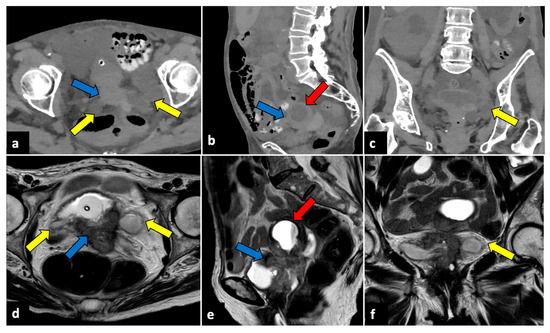

Gynaecological Causes of Acute Pelvic Pain: Common and Not-So-Common Imaging Findings

by Paolo Niccolò Franco, Alejandra García-Baizán, María Aymerich, Cesare Maino, Sofia Frade-Santos, Davide Ippolito and Milagros Otero-García

Life 2023, 13(10), 2025; https://doi.org/10.3390/life13102025 - 9 Oct 2023

In female patients, acute pelvic pain can be caused by gynaecological, gastrointestinal, and urinary tract pathologies. Due to the variety of diagnostic possibilities, the correct assessment of these patients may be challenging. The most frequent gynaecological causes of acute pelvic pain in non-pregnant women are pelvic inflammatory disease, ruptured ovarian cysts, ovarian torsion, and degeneration or torsion of uterine leiomyomas. On the other hand, spontaneous abortion, ectopic pregnancy, and placental disorders are the most frequent gynaecological entities to cause acute pelvic pain in pregnant patients. Ultrasound (US) is usually the first-line diagnostic technique because of its sensitivity across most common aetiologies and its lack of radiation exposure. Computed tomography (CT) may be performed if ultrasound findings are equivocal or if a gynaecologic disease is not initially suspected. Magnetic resonance imaging (MRI) is an extremely useful second-line technique for further characterisation after US or CT. This pictorial review aims to review the spectrum of gynaecological entities that may manifest as acute pelvic pain in the emergency department and to describe the imaging findings of these gynaecological conditions obtained with different imaging techniques. Full article

Figure 1